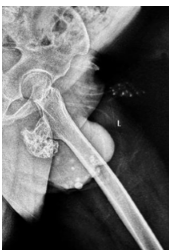

Migration of Two Broken K-wires into the Cervical Region following Lateral End Clavicle Fixation: A Rare Case Report and Literature Review

Sujit Kumar Tripathy , Shahnawaz Khan , Hrudeswar Behera , Gandharav Mehta , Dillip Kumar Sasmal , Mantu Jain